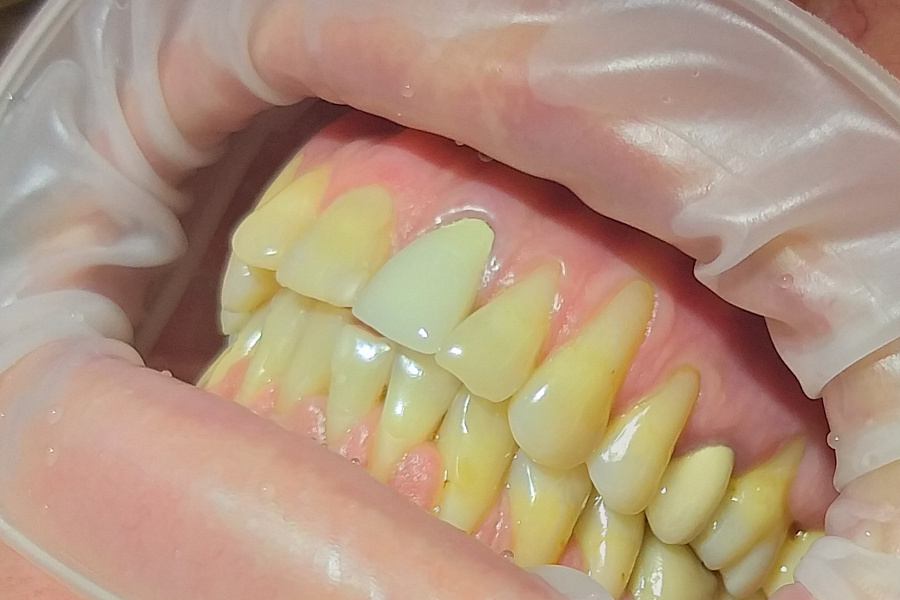

Пациент обратился в клинику с жалобами на оголение шеек и корней зубов, повышенную чувствительность зубов от холодного, горячего и других пищевых раздражителей, боли во время чистки зубов, косметический дефект.

Поставлен диагноз генерализованная рецессия десны в области зубов верхней и нижней челюстей, аномалии положения зубов

1. Ортодонтическое лечение, чтобы восстановить правильное положение зубов верхней и нижней челюстей. Лечение проводила Кобликова Анастасия.